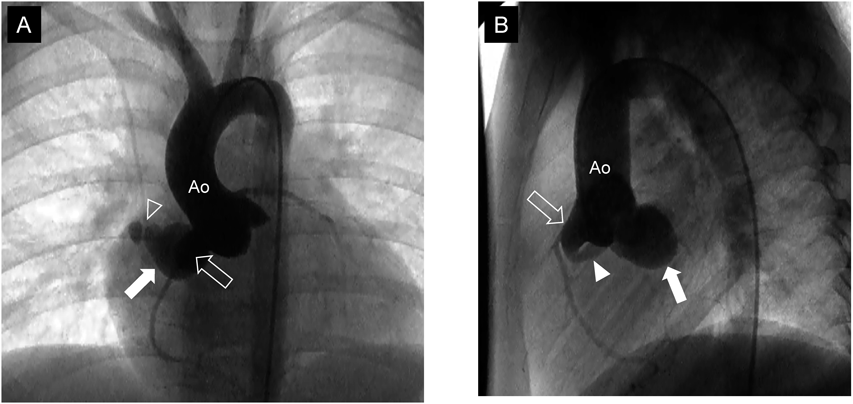

Fig. 1 Two-dimensional echocardiography at 9th day (A) and at 12th day of illness (B)

Note that the right coronary artery (open arrow) was enlarged and connected to coronary artery fistula (solid arrowhead), which had aneurysmal formation (solid arrow) at the distal portion. Ao, the ascending aorta.